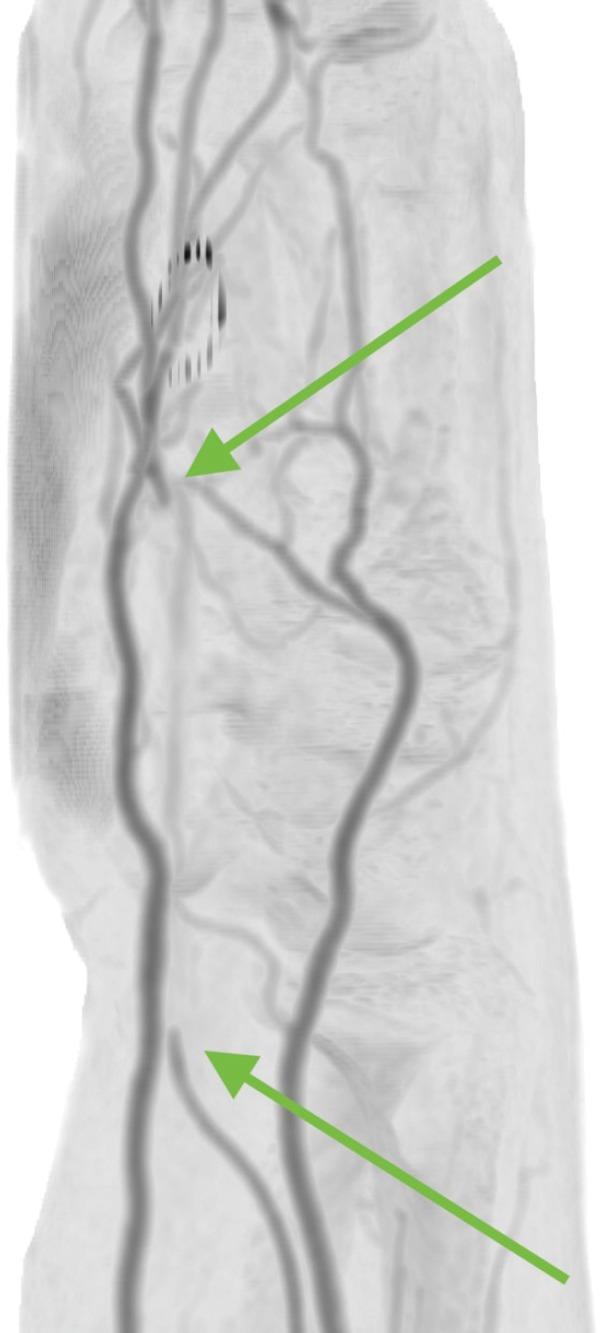

: Carpal tunnel syndrome (CTS) is a sporadic event with compression of the median nerve (MN). Persistent median artery (PMA) thrombosis is an exceptionally rare cause of CTS. : 38-year-old male presented with acute on subacute right wrist pain with positive Tinel's sign. An ultrasound and computed angiography study confirmed a PMA with thrombosis. The patient was treated with intravenous heparin then discharged home on enoxaparin and warfarin crossover. : PMA can lead to CTS by compression from the adjacent median nerve. Thrombosis of the PMA can also lead to CTS. Surgical intervention is needed in cases of severe CTS. Carpal tunnel release is usually successful. Excision of the PMA can risk vascular compromise of the digits. Ultrasound is excellent for detecting rare causes of CTS. : Ultrasound examination for CTS should include search for PMA and associated anatomical variations.

腕管综合征(CTS)是一种因正中神经(MN)受压引起的散发性疾病。持续性正中动脉(PMA)血栓形成是CTS极为罕见的病因。一名38岁男性因亚急性右腕疼痛伴Tinel征阳性就诊。超声和计算机血管造影检查证实存在PMA伴血栓形成。患者先接受静脉肝素治疗,然后出院时改用依诺肝素和华法林交叉治疗。PMA可通过对相邻正中神经的压迫导致CTS。PMA血栓形成也可导致CTS。严重CTS病例需要手术干预。腕管松解术通常很成功。切除PMA可能会有手指血管受损的风险。超声对于检测CTS的罕见病因非常有效。对于CTS的超声检查应包括寻找PMA及相关解剖变异。